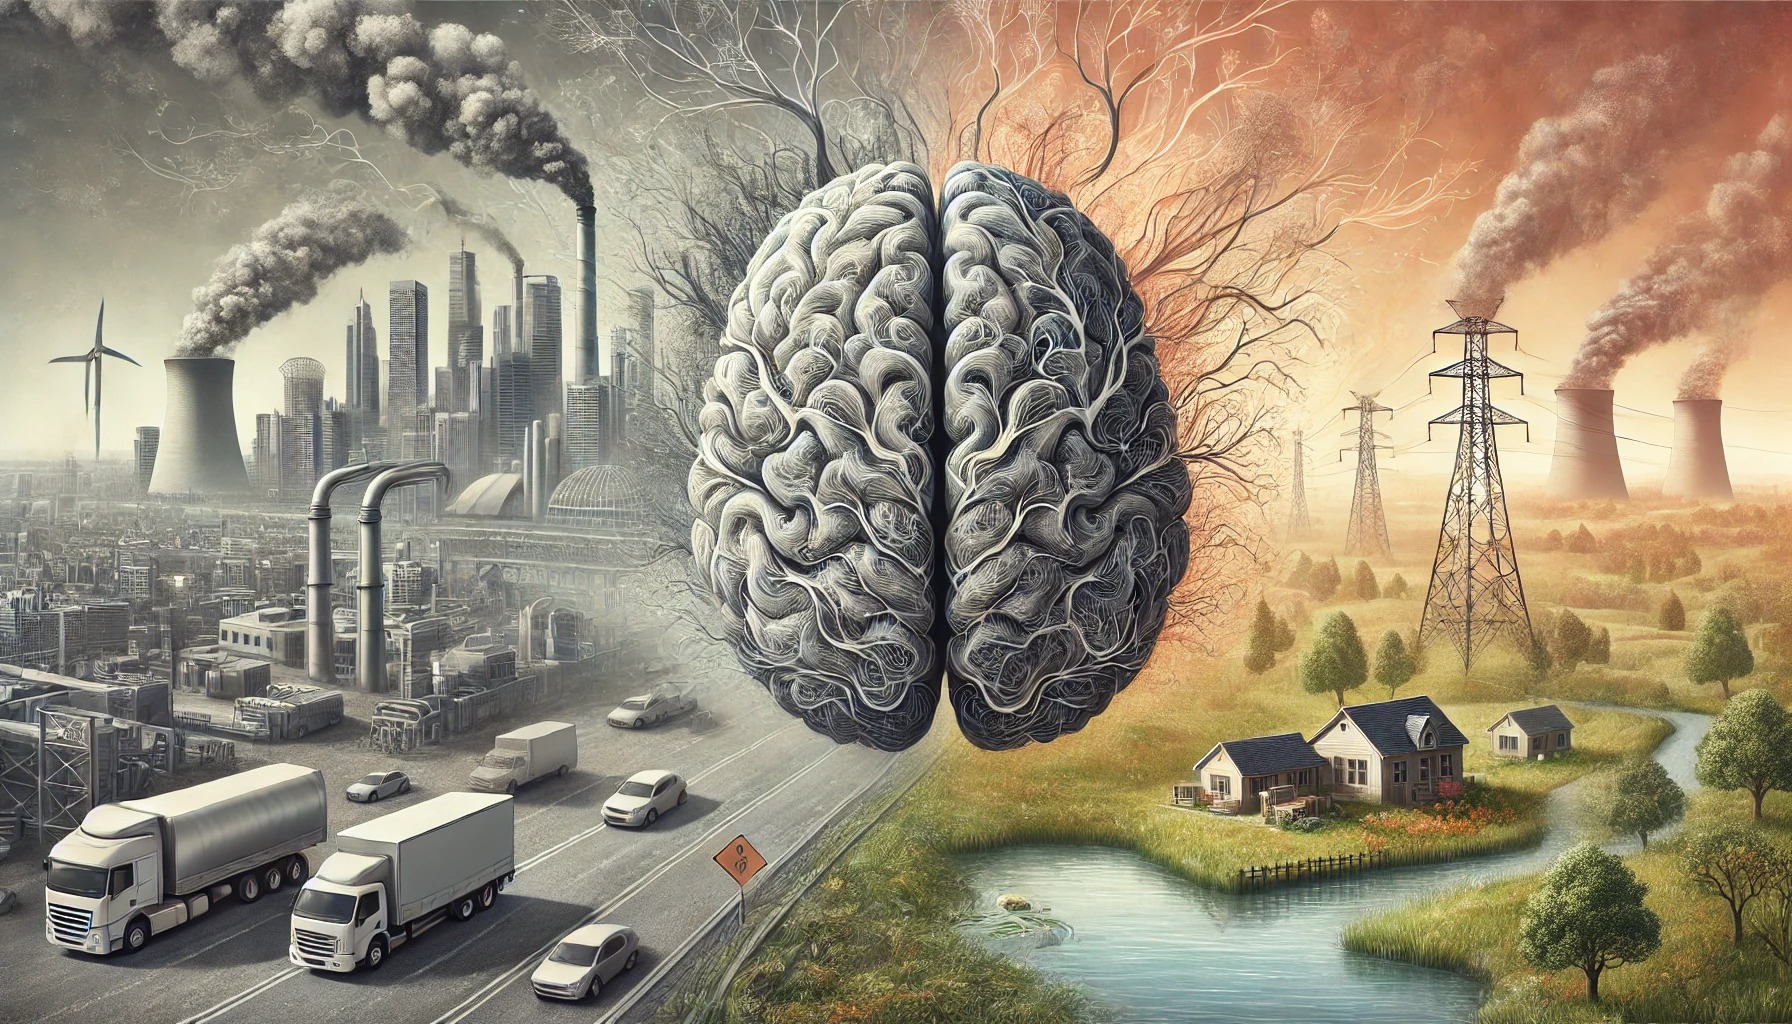

Inflammation Unleashed

Inflammation is a core part of the immune system response for the brain and body. With age, low-grade chronic inflammation can develop—a phenomenon scientists call inflamm-aging. This process can make the brain more vulnerable to age-related diseases, especially if there is a history of other inflammatory events like a traumatic brain injury. Alzheimer’s-related damage to brain cells causes a significant increase in inflammation— a double-edged sword that can cause further damage.

Alzheimer’s Disease Research grantee Dr. David Gate is investigating how immune cells in the blood and an individual’s environment can contribute to inflammation in Alzheimer’s. Learn more.